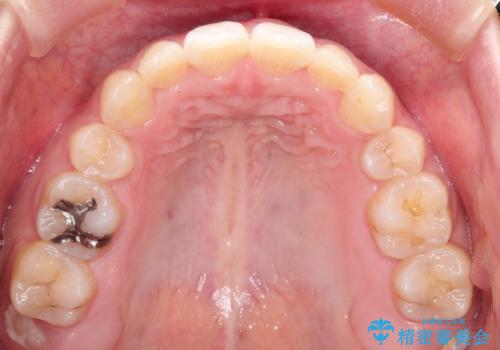

乳歯を抜歯することにより、通常よりは治療期間を要してしまいましが、前歯のガタガタもなくなりきれいな歯並びになったと喜んでいただけました。

- 2年6ヶ月

- 治療回数

- 10-30回